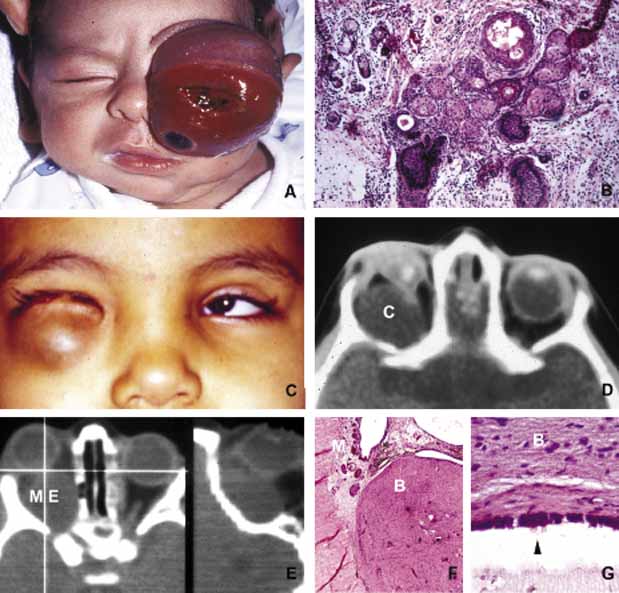

Fig. 1 Congenital lesions. A very large cystic teratoma of a 1-month old child (A). B. Histology of this lesion that contains a variety of tissues, endodermal, ectodermal, and mesenchymal. An orbital cyst (C) in an orbit containing micro-ophthalmic globe. C, D. The protrusion of the cyst inferiorly creates a mechanical lower lid ptosis that narrows the right maldeveloped conjunctival sac even further. Axial and sagittal CT scan showing a meningoencephalocele (ME) occupying the entire orbit (E). The histopathologic examination of the lesion revealed both meningeal (M) and brain (B) tissues (F). The high-power histopathology reveals ciliated ependymal cells lining some of the cystic spaces (arrowhead) (G).

Cephalocele results from the extension of maldeveloped CNS tissues including meninges (meningocele), brain parenchyma (encephalocele), and the combination of the two (meningoencephalocele) into the orbital cavity.12,13 Intraorbital cephaloceles may develop anteriorly at the suture lines of orbital bones or posteriorly extending into the orbit from orbital fissures and the optic canal. Depending on the combination of these herniations they contain brain and/or meningeal tissues (Fig. 1). Aberrant fibroglial tissue has also been described in the orbit.14

Teratoma is a germ-cell tumor that contains tissues derived from endoderm, ectoderm, and mesoderm22 (Fig. 1). Therefore, these lesions may contain skin, bowel, lung, brain, thyroid, cartilage, and bone tissues. Most teratomas develop unilaterally and in girls. A majority of these congenital tumors are benign. Occasional reports have documented malignant transformation within orbitocranial teratomas.23 However, these benign tumors continue to grow after birth because of the collection of secretions from different tissues into the partially cystic spaces of the tumor. Some teratomas create massive proptosis and most can only be treated by exenteration. However, some of these lesions have recently been reported to be removed surgically with preservation of the globe and other vital orbital structures.